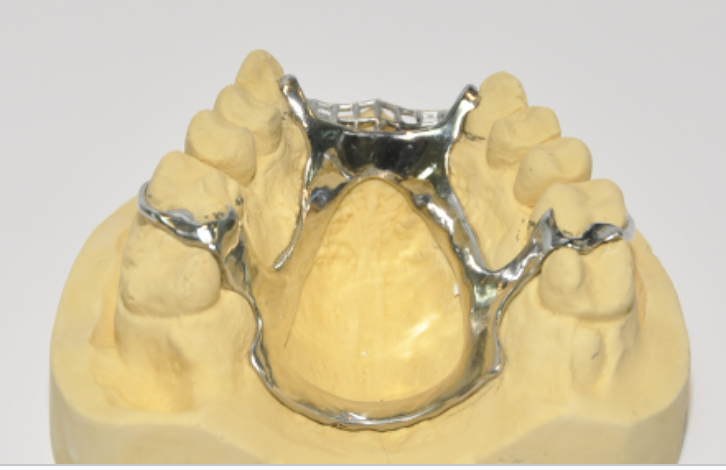

Classify by the denture material

All acrylic - acrylic denture

Metla framework bt teeth and gum cyclic - cobalt chrome

Cobalt chrome used to make the metal for the frame

Cobalt chrome

Stronger

Cut away from gingival margin

Patient gets their taste sensations back

More retentive and stays in better than acrylic denture might do

Only for patients who have a stable mouth which may lead to further loss of tooth

More expensive than acrylic